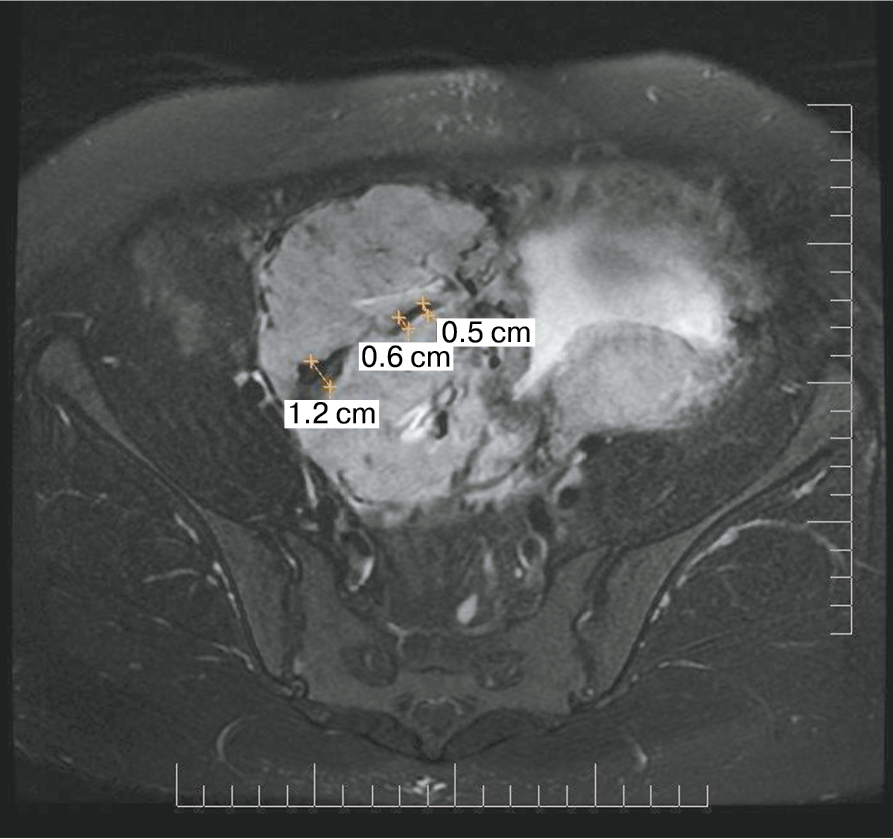

Является ли симптом «обнаженного сосуда» патогномоничным для параметральной инвазии или нет, еще предстоит выяснить; однако в ходе исследования установлена его связь с частотой гистерэктомий в группах с наличием симптома «обнаженного сосуда», что, вероятно, обусловлено мощной сосудистой сетью коллатералей и неоангиогенезом. Во всех случаях обнаружения данного признака впоследствии была выполнена вынужденная гистерэктомия (рис. 3–6, пациентка Н., 37 лет).

Рис. 6. Корональная проекция МРТ. 1 – обнаженный сосуд; 2 – интрамуральная гиперваскуляризация; 3 – гиперваскуляризация плаценты